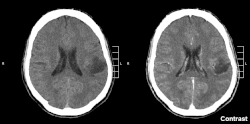

Glioma in the left parietal lobe (brain CT scan), WHO grade 2